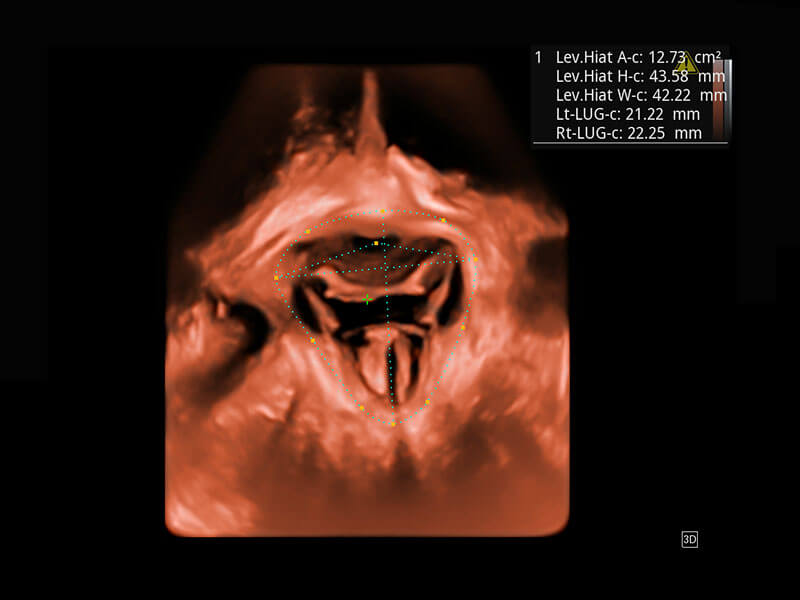

盆底超声

P60为盆底超声检查提供全面的应用方案,多种腔内及腹部容积探头提供从二维、三维到四维的优异图像品质,实时快速三维容积数据获取,专业的测量工具包等人性化设计,为超声医生诊断提供有力保障。

Lev.Hiat A-r: 16.33 cm2

Lev.Hiat H-r: 53.70 mm

Lev.Hiat W-r: 43.96 mm

Lt-LUG-r: 24.16 mm

Rt-LUG-r: 19.94 mm

S-Pelvic